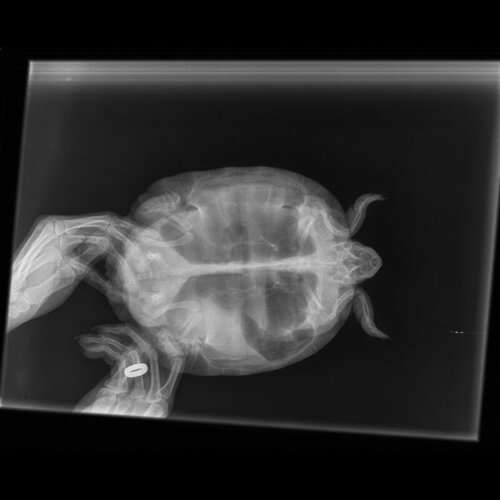

Добрый день.Вчера делали рентген красноухой черепахе,ей ставили диагноз пневмония 14 мая, кололи антибиотик Байтрил  12 дней и Дексометазон 7 дней, глюкозу 4 дня,так как ничего не ест. Если кто-то может и понимает в рентгене, прошу проконсультировать.

по такой проекции невозможно увидеть лёгкие черепахи и подтвердить или опровергнуть пневмонию